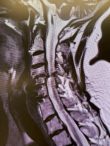

William J. Sonstein, M.D., F.A.C.S. is a Board-Certified Diplomate, American Board of Neurosurgery. He has a special interest in complex spine surgery and has one of the largest experiences with Posterior Lumbar Interbody Fusion (PLIF) on Long Island. This procedure relieves pain for patients with intractable back pain. Dr. Sonstein uses minimally invasive procedures whenever possible, such as Kyphoplasty and X-STOP™ to treat spinal compression fractures and spinal stenosis.

Case Studies